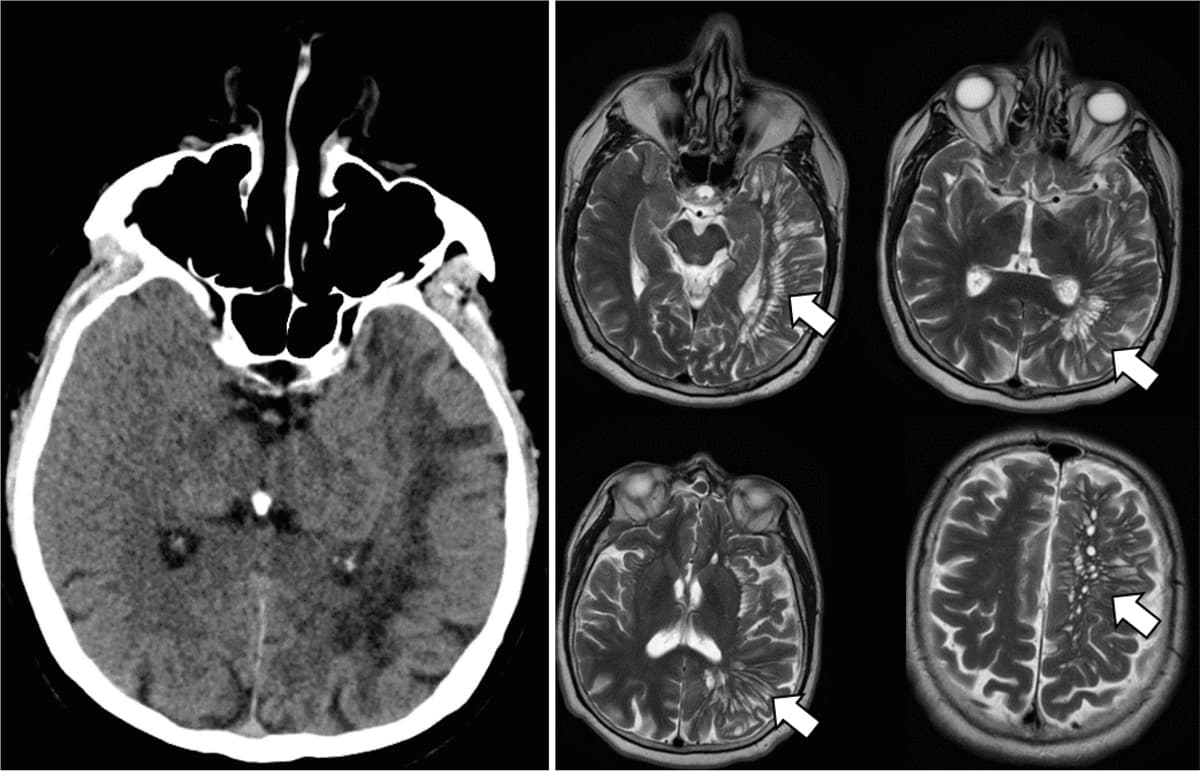

En mand på 70 år, tidligere rask, blev henvist af egen læge pga. tre års tiltagende ordfindingsbesvær og en CT, som gav mistanke om ældre infarkter i hele venstre hemisfære. Objektivt havde patienten svært ved at mobilisere dyrenavne og s-ord, men var ellers upåfaldende. En supplerende MR-skanning viste udvidede perivaskulære rum (PVS) i hele venstre hemisfære, uden tegn til iskæmi. En neuropsykologisk undersøgelse viste let påvirkning af de eksekutive funktioner, foreneligt med mild kognitiv impairment.

PVS er fyldt med interstitiel væske, som omkranser penetrerende kar fra subaraknoidalrummet ind i hjernevævet [1]. Prævalensen af MR-påvist dilaterede PVS er 1,6-3% blandt raske [2]. Undertiden bliver de svært forstørrede (kaldet gigant-PVS) med neurologiske udfald til følge [3]. Differentialdiagnoser er iskæmi, inflammation og cystiske neoplasier [2]. De adskilles fra lakunære infarkter ved at være mere afrundede og uden gliose. Hos denne patient var alle tre venstre kargebeter afficeret, hvilket er sjældent ved iskæmiske læsioner. PVS-ætiologien er uafklaret, men antages at være en normalanatomisk variant eller et udtryk for cerebral atrofi frem for en sygdomsproces i sig selv.